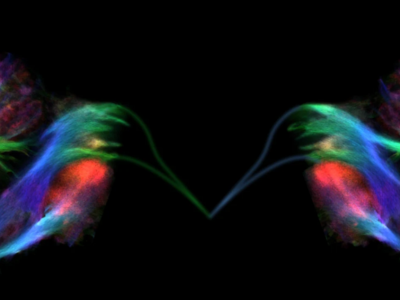

No 10 | Tractographie du cervelet